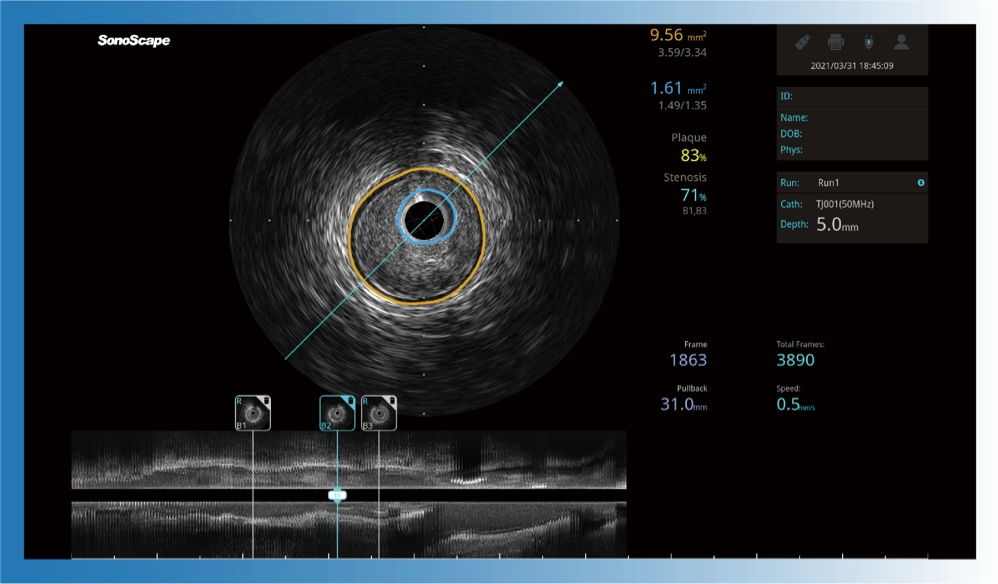

对比传统IVUS导管成像,银河集团官网宽频IVUS图像的近场支架梁显影更细腻,远场中膜外血管仍清晰可辨,兼顾远中近,兼顾分辨力与穿透深度

一键智能描迹,自动测量斑块负荷、面积狭窄率等指标,准确率高于90%